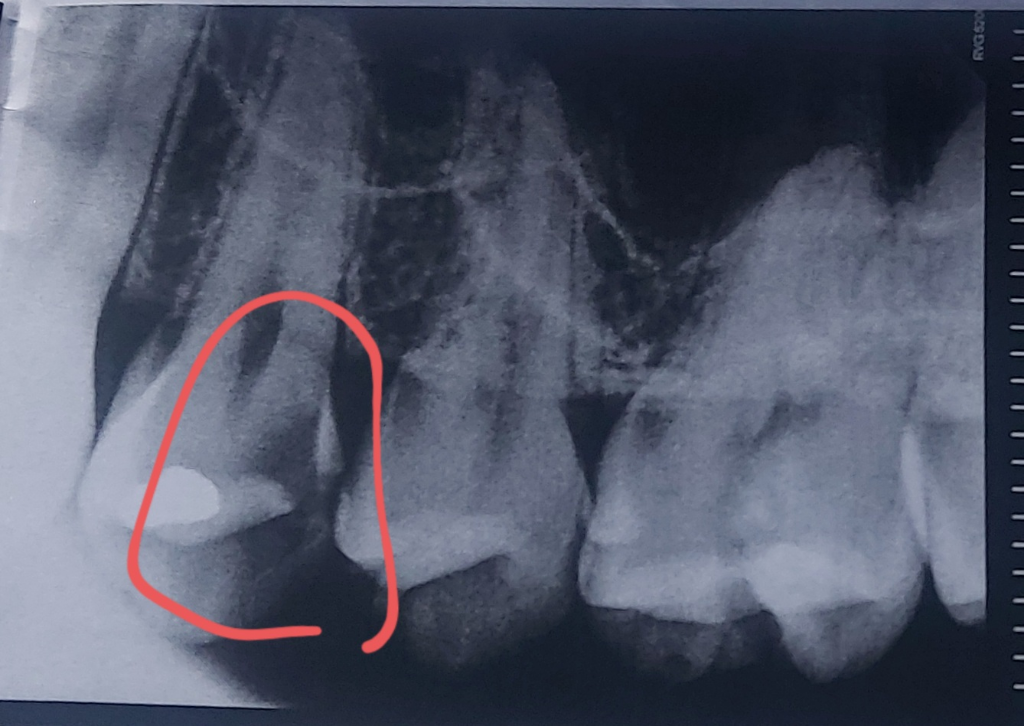

차가운거 먹었을 때 이가 시린 증상이 있어서 오늘 치과에 가서 검진을 받았습니다

육안으로 보이는 충치는 없어서 바람 쏘면서 시린지 물어보셨고 시리지 않다고 하니 아이스막대로 확인해보셨습니다. 시린 증상 있는 이가 총 두 개 였구요 그 두 개만 집중적으로 사진 찍어서 보여주셨습니다

사진 보시자마자 두 개 다 신경치료해야한다고 하시던데 제가 일단 검진만 계획하고 와서 다음에 다시 오겠다하니

+추가로 첫번째 사진에 검은 부분이 충치라면 육안으로 확연히 보이거나 어두운 빛으로라도 보여야하는 거 아닌가요 육안으로 봤을 땐 어두운 부분도 없고 별다른 이상이 없어보입니다...

• 1번 째 사진

사진상으로는 신경치료를 해야될 가능성이 높습니다만

충치는 제거를 해봐야 확실히 알 수 있습니다

엑스레이 상으로 봐도 충치가 깊어 보입니다. 신경치료를 해야될 가능성이 높아 보이네요.